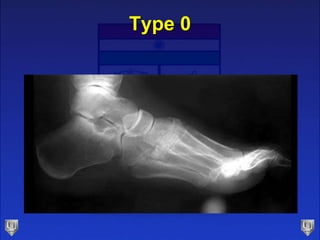

Type 0

Type 1